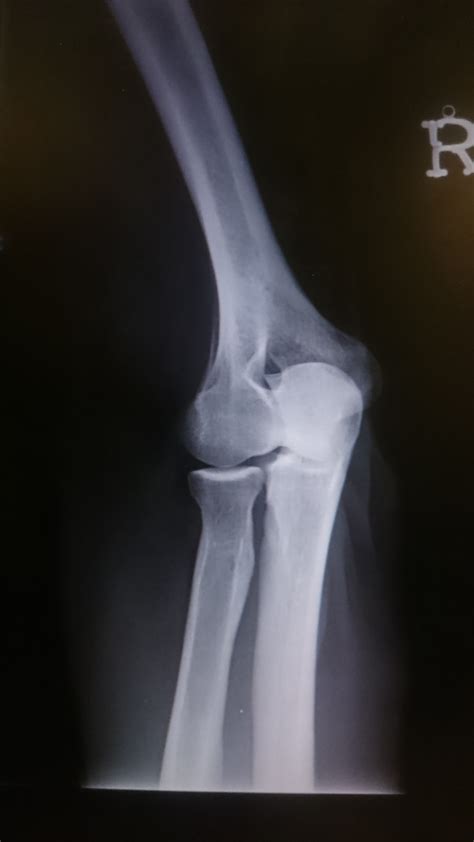

Posterior Impingement Test | Internal Shoulder Impingement